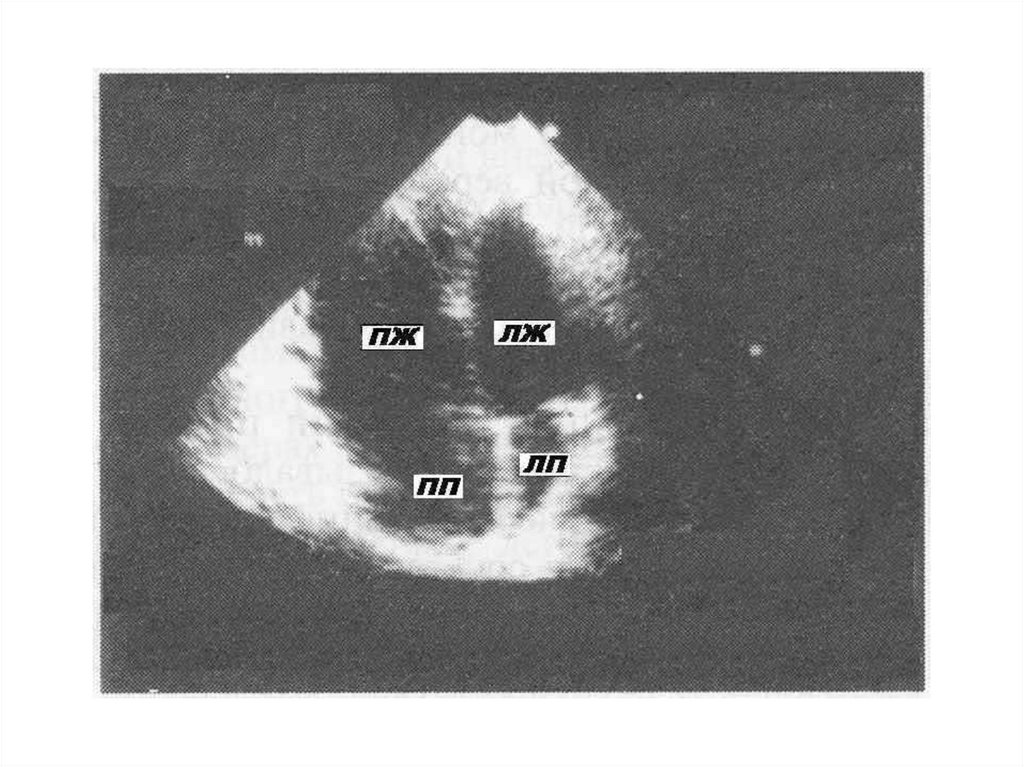

ЭхоКГ критерии ГКМП

Показатель

Диагностический критерий

Толщина передне-перегородочного и

заднего сегментов ЛЖ

≥ 13 мм

Толщина задне-перегородочного и

бокового сегментов ЛЖ

≥ 15 мм

Соотношение толщины МЖП / ЗСЛЖ

> 1,3

Размер левого предсердия

увеличен

Объём полости ЛЖ

нормальный или снижен

Фракция выброса

нормальная или повышена

Диастолическая функция

нарушена

11. ЭхоКГ- признаками обструкции выносящего тракта ЛЖ являются:

• наличие систолического движения вперёд

передней (иногда и задней) створки

митрального клапана и её соприкасание с

МЖП, занимающее иногда до1/3 систолы;

• частичное систолическое прикрытие створок

аортального клапана в момент митральносептального контакта;

• наличие митральной регургитации;

• наличие градиента давления (по данным

допплер-ЭхоКГ).